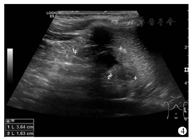

18例患儿术后随访时间范围为3~19个月,RALUR组及LUR组各有2例因尿路感染行抗感染治疗,拔除双J管后好转。术后超声检查显示RALUR组10例输尿管扩张中9例恢复正常,7例肾积水较前明显缩小;LUR组8例输尿管扩张均恢复正常,5例肾积水较前明显缩小(图4)。18例患儿术后3个月复查排泄性膀胱造影均未见明显反流。